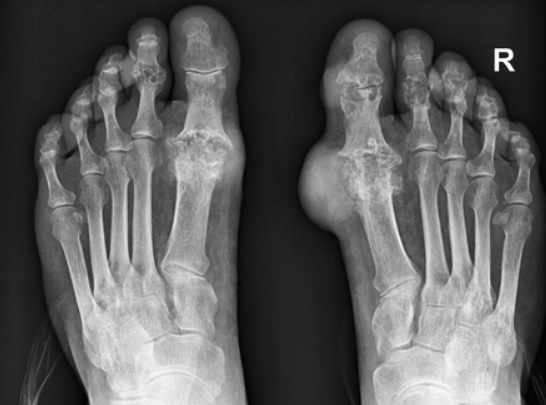

만성 통풍은 급성 통풍 발작 이후에 발생하는 상태로, 통증이 잦은 발작으로 일어나지 않으며, 영구적인 조직 손상을 초래할 수 있습니다. 만성 통풍은 발적 부위의 결절, 증식된 발적 또는 발작 없이 발적 부위가 늘어나는 것으로 나타날 수 있습니다.

통풍 진단

의사는 통풍을 의심할 경우 환자의 증상 및 혈액 검사, 요산 수치 측정, 관절 내 유체 검사 등을 통해 진단할 수 있습니다.